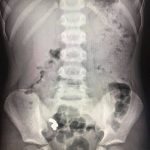

Нещодавно у місцеве хірургічне відділення поступив п’ятирічний хлопчик – за 17 днів до цього він проковтнув сім дрібних магнітних кульок з іграшки. І хоч скарги на самопочуття у дитини були відсутні, під час рентгенологічного дослідження діагностували наявність магнітів в кишечнику, які не просуваються протягом 10 днів. Це стало показанням до оперативного втручання, пише “Галка”.

Вже під час операції медики виявили зрощення стінки тонкої кишки, де розташовані 4 магніти, із стінкою сліпої кишки, де виявлено 3 магніти. Фахівці видалили зайві предмети та провели необхідні лікувальні маніпуляції з кишками. В підсумку обійшлося без небезпечних ускладнень.